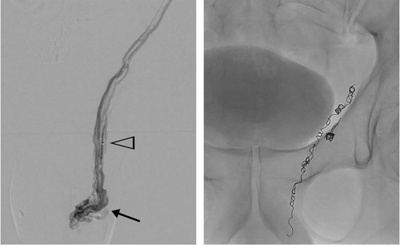

In Lokalanästhesie wird in der Leiste ein Katheter eingebracht, der unter Röntgen-Kontrolle über die Nierenvene in die Hodenvene (Vena spermatica) vorgeschoben wird. Mit Kontrastmittel werden die betroffenen Venen sichtbar gemacht. Diese Venen werden dann mit Metallspiralen (Coils) wie eine Staumauer verschlossen. Die Dauer des praktisch schmerzfreien und sehr komplikationsarmen Eingriffs beträgt ca. 45 Minuten.

Katheterembolisation eine Varikozele links. Darstellung der krampfartig erweiterten Venen im Bereich des linken Hodens (Pfeil) nach Kontrastmittel-Injektion über den in die Hodenvene (Vena spermatica) vorgeschoben Katheter (Pfeilspitze). Nachfolgend Verschluss der erkrankten Venen mittels Metallspiralen (Coils).